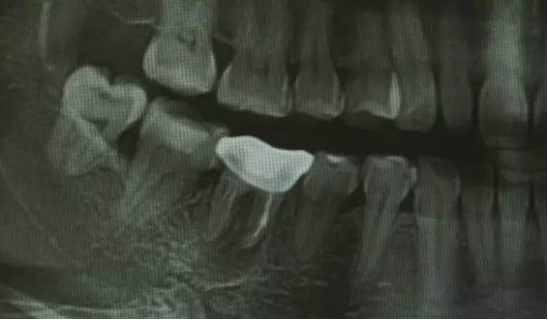

上、下颌骨形态及位置关系判断